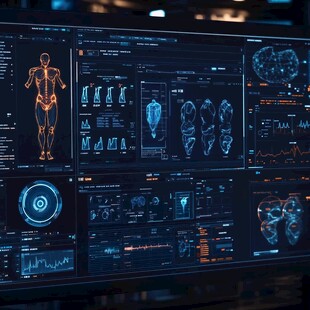

医学界面设计 非商作品

医学界面设计 非商作品 -